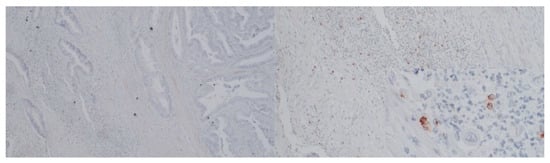

In a randomly selected 24 cases, immunostaining for RANTES and PD-L1 (Figure 4 and Figure 5) was performed. In six different specimens, tumor cells were positive for RANTES and PD-L1. We did not observe any significant associations between RANTES and PD-L1 expression in the tumor, TILs and clinicopathological features of the patients (Table 10, Table 11 and Table 12).

Figure 4. Immunostaining for RANTES (Opta Tech 2200 Camera, magnification 10× and 60×). Cytoplasmatic positive IHC staining for RANTES in tumor-infiltrating lymphocytes.

Figure 5. Immunostaining for PD-L1 ((Opta Tech 2200 Camera, magnification 10× and 60×). Cytoplasmatic positive IHC staining for PD-L1 in tumor-infiltrating lymphocytes.